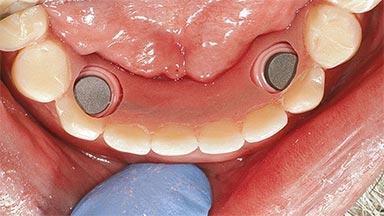

Improving an Existing Implant-supported Denture in an Alzheimer Patient with Bipolar Affective Disorder with Moderate Depression and Dementia

An 83-year-old man presented together with his caregiver at the dental department of the Medical University of Innsbruck, Austria with complaints of swelling in the right maxillary canine area and loss of retention of his 5-years-old mandibular denture. The patient had a significant medical history (20 years) of bipolar affective disorder with moderate depression (F 31.3) and dementia in Alzheimer’s disease (F 00.2). The patient had been in ambulant psychiatric therapy for his depressive illness for the past 20 years. He lived alone and had no children; his sister assisted with daily living. She reported that the patient exhibited compulsive hoarding behavior. In the previous two months, she had noted increasing disorientation and vertigo in the patient. She therefore accompanied him for a medical consultation at the Department of Psychiatry and Psychotherapy of the Medical University of Innsbruck. He was released home after a 6-week inpatient stay.

# of Implants 2

Type of Implants One-Piece

Attachment One-Piece

Prosthesis Type RDP